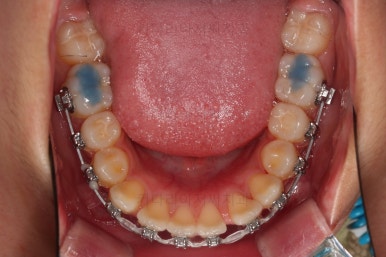

1. 초진 시 입안의 모습 평가

부산치아교정치과 키다리아저씨치과에 처음 내원했을 당시의 입 안의 모습입니다.

전반적으로 윗니가 나와있는 양상이고요.

앞니는 뻐드러져 있네요.

아래 앞니는 위로 솟구쳐 올라서 윗니 뒤쪽을 강하게 치고 있는 과개교합 양상이었고요.

위아래 앞니쪽이 삐뚤어져 있는 상태였습니다.

우선 윗니만 장치를 부착했습니다.

순서는 윗니 장치 부착 후 발치를 하고, 가지런하게 된 뒤에, 과개교합 개선을 위한 특별한 장치가 들어가면서 아랫니에도 브라켓을 부착하기로 정했습니다.

윗니가 가지런해진 뒤에는 부산치아교정치과 키다리아저씨치과에서는 ABP라고 하는 장치를 사용해 주면서 아랫니에도 브라켓을 부착합니다.

깊게 물리는 과개교합을 개선하기 위함인데요.